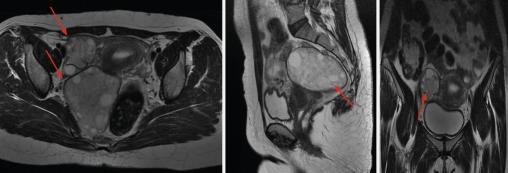

Une patiente âgée de 44 ans, opérée pour un kyste hydatique hépatique seize ans auparavant, consulte pour des douleurs abdomino-pelviennes intermittentes et une irrégularité du cycle menstruel. L‘examen clinique révèle une masse annexielle droite, sensible et indépendante de l’utérus ainsi qu’une hépatosplénomégalie. L’état général est conservé. L’hémogramme montre une hyperleucocytose à 24 800/mm3 à prédominance de neutrophiles et une anémie hypochrome microcytaire. La sérologie hydatique est positive. L’échographie pelvienne met en évidence deux formations en régions ovarienne et rétro-utérine droites, bien limitées, renfermant plusieurs structures serpigineuses rappelant des membranes proligères, et des images multi­vésiculaires, mesurant 42 × 40 mm et 80 × 73 mm. Ces observations permettent d’évoquer le diagnostic de kyste hydatique ovarien organique classé type III de la classification de Gharbi. Le balayage hépatosplénique trouve des kystes hydatiques spléniques et hépatiques du segment IV classés type III de la classification de Gharbi. La tomodensitométrie (TDM) abdomino-pelvienne (fig. 1) confirme la présence de deux formations ovariennes et rétro-utérines droites ovalaires, mal limitées, à paroi fine, de densité liquidienne, qui renferment une membrane décollée avec une localisation hépatosplénique. L’imagerie par résonance magnétique (IRM) pelvienne (fig. 2 et 3) précise l’aspect des deux volumineuses masses : une latéro-utérine et l’autre rétro-utérine à droite, de contours réguliers, bien limitées, à paroi fine, de signal hétérogène T2, renfermant des vésicules filles en hypersignal T2 franc liquidien sans restriction de la diffusion et ne se rehaussant pas après injection. La patiente a bénéficié d’une intervention chirurgicale, qui a trouvé deux kystes pelviens latéro-utérins de 8 cm de diamètre pour le plus volumineux. L’étude anatomopathologique a confirmé le diagnostic de kyste hydatique.  Les suites postopératoires ont été simples, avec un traitement médical adjuvant par albendazole.